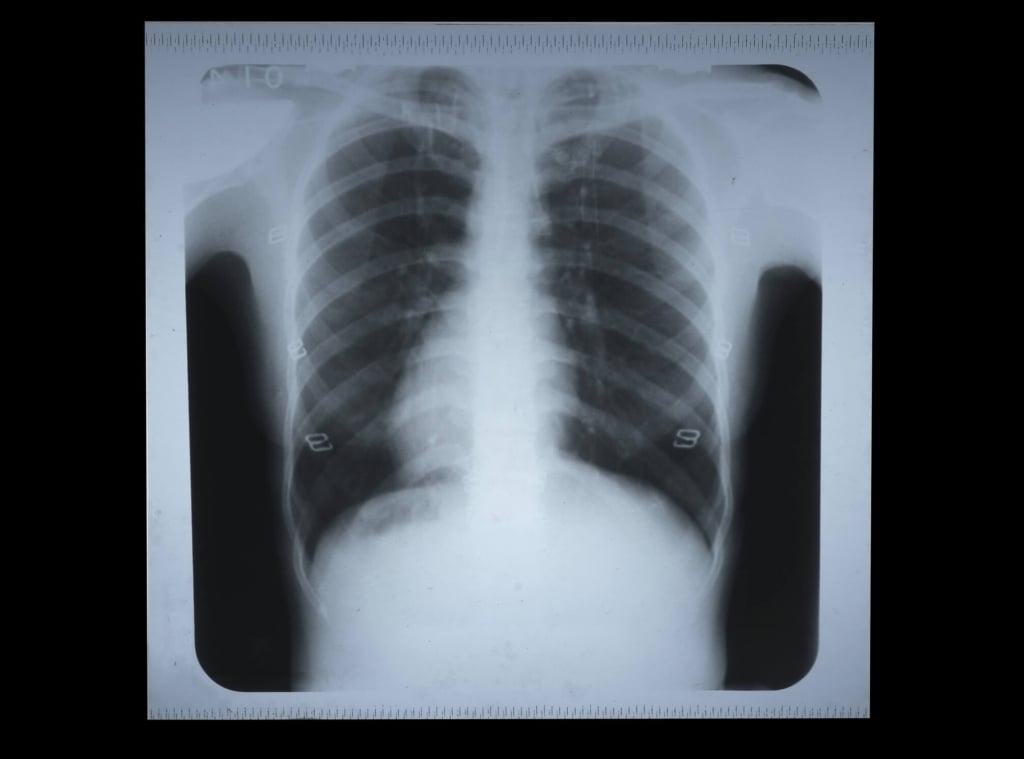

Ecco come cambia il rischio di sviluppare alcune delle principali malattie legate all'uso di tabacco.